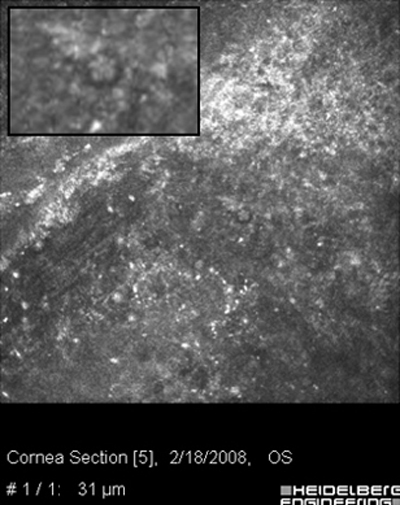

Ante la sospecha por los antecedentes e imágenes biomicroscópicas de una queratitis por Acantamoeba, debe hacerse su confirmación diagnóstica mediante extendidos de la superficie corneal para estudio microscópico, con las imágenes obtenidas “in vivo” con microscopía confocal (Figura 31 y 32) y mediante cultivos del parásito.

Acanthamoeba Microscopía Confocal

Fig. 31 Microscopía Confocal

Comparar Microscopía Confocal

Fig. 32 Comparar con quiste Acanthamoeba Fig 39